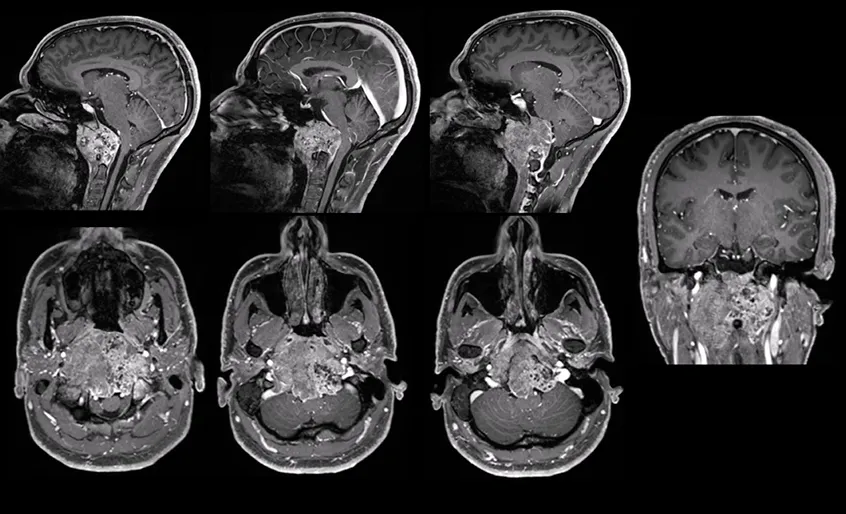

肿瘤的侵犯范围如此之大,意味着治疗将面临重重障碍:手术全...